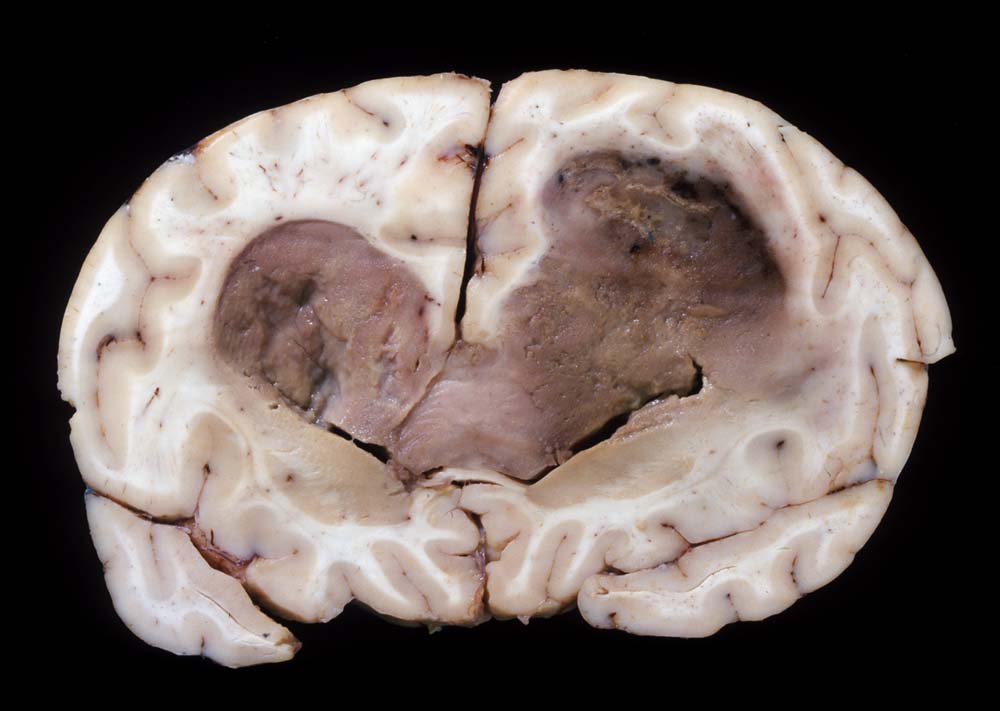

PathoPic – image database / PathoPic ID 9022 - Glioblastoma multiforme

Glioblastoma multiforme

Beginnend im Marklager des rechten Frontallappens, findet sich eine zystische bräunliche Raumforderung mit perifokalem Ödem, welche sich in dorsaler Richtung den Balken infiltrierend in das Marklager der linken Hemisphäre ausdehnt. Die Raumforderung ist von weicher Konsistenz mit teils nekrotischen Arealen und von graubrauner, teilweise auch gelblicher Farbe. Sie dehnt sich in beiden Hemisphären aus, wächst in die Seitenventrikel ein und füllt diese zum Teil komplett aus. Hirnödem mit verbreiteten Gyri.

Seit zwei Monaten frontale Kopfschmerzen. CT- und MRI-Untersuchungen zeigten eine bifrontale interkranielle Raumforderung. Bioptische Diagnose eines Glioblastoma multiforme.